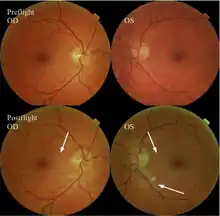

The first U.S. case of visual changes observed on orbit was reported by a long-duration astronaut that noticed a marked decrease in near-visual acuity throughout his mission on board the ISS, but at no time reported headaches, transient visual obscurations, pulsatile tinnitus or diplopia (double vision). His postflight fundus examination (Figure 1) revealed choroidal folds below the optic disc and a single cotton-wool spot in the inferior arcade of the right eye. The acquired choroidal folds gradually improved, but were still present 3 year postflight. The left eye examination was normal. There was no documented evidence of optic-disc edema in either eye. Brain MRI, lumbar puncture, and OCT were not performed preflight or postflight on this astronaut.[5]

The third case of visual changes while on board the ISS had no changes in visual acuity and no complaints of headaches, transient visual obscurations, diplopia or pulsatile tinnitus during the mission. Upon return to Earth, no eye issues were reported by the astronaut at landing. Fundus examination revealed bilateral, asymmetrical disc edema. There was no evidence of choroidal folds or cotton-wool spots, but a small hemorrhage was observed below the optic dics in the right eye. This astronaut had the most pronounced optic-disc edema of all astronauts reported to date, but had no choroidal folds, globe flattening or hyperopic shift. At 10 days post landing, an MRI of the brain and eyes was normal, but there appeared to be a mild increase in CSF signal around the right optic nerve.[5]

The sixth case of visual changes of an ISS astronaut was reported after return to Earth from a 6-month mission. When he noticed that his far vision was clearer through his reading glasses. A fundus examination performed 3 weeks postflight documented a grade 1 nasal optic-disc edema in the right eye only. There was no evidence of disc edema in the left eye or choroidal folds in either eye (Figure 13). MRI of the brain and eyes days postflight revealed bilateral flattening of the posterior globe, right greater than left, and a mildly distended right optic nerve sheath. There was also evidence of optic-disc edema in the right eye. A fundus examination postflight revealed a "new onset" cotton-wool spot in the left eye. This was not observed in the fundus photographs taken 3 weeks postflight.[5]

The seventh case of visual changes associated with spaceflight is significant in that it was eventually treated postflight. Approximately 2 months into the ISS mission, the astronaut reported a progressive decrease in his near and far acuity in both eyes. The ISS cabin pressure, CO2 and O2 levels were reported to be within normal operating limits and the astronaut was not exposed to any toxic substances. He never experienced losses in subjective best-corrected acuity, color vision or stereopsis. A fundus examination revealed a grade 1 bilateral optic-disc edema and choroidal folds (Figure 15).[5]